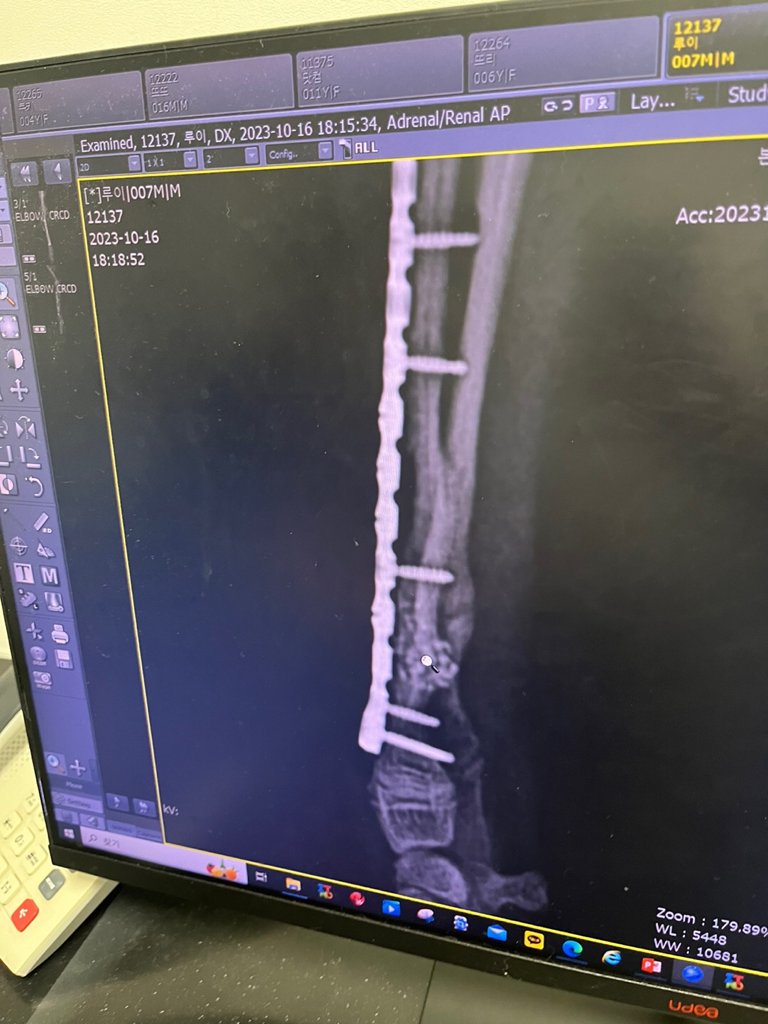

요척골 골절 후 재골절 수술하였는데 아이가 다리에 힘을 아예 안 넣어요

요척골 골절로 수술을 하고 재골절이 되어 다시 재수술을 하고 4주 깁스 후에 울타리에 운동제한을 하였습니다. 깁스를 푼 지 1주일이 지났는데, 그때는 다리를 쓰거나 정상적일 거라고 하였는데, 아이를 들고 흔들어보면, 재골절 되었을 때의 흔들림 같고, 힘을 아예 안 넣습니다. 걷는 건 잘 걷습니다